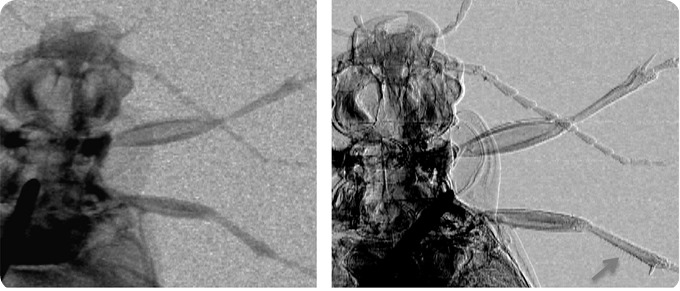

Attentuation (left) and phase (right) images of a ground beetle. The arrow in the bottom right corner of the latter image shows how thin hairs on the insect’s leg are visualized thanks to phase effects. Credit: Advanced X-Ray Imaging (AXIm) Group, UCL